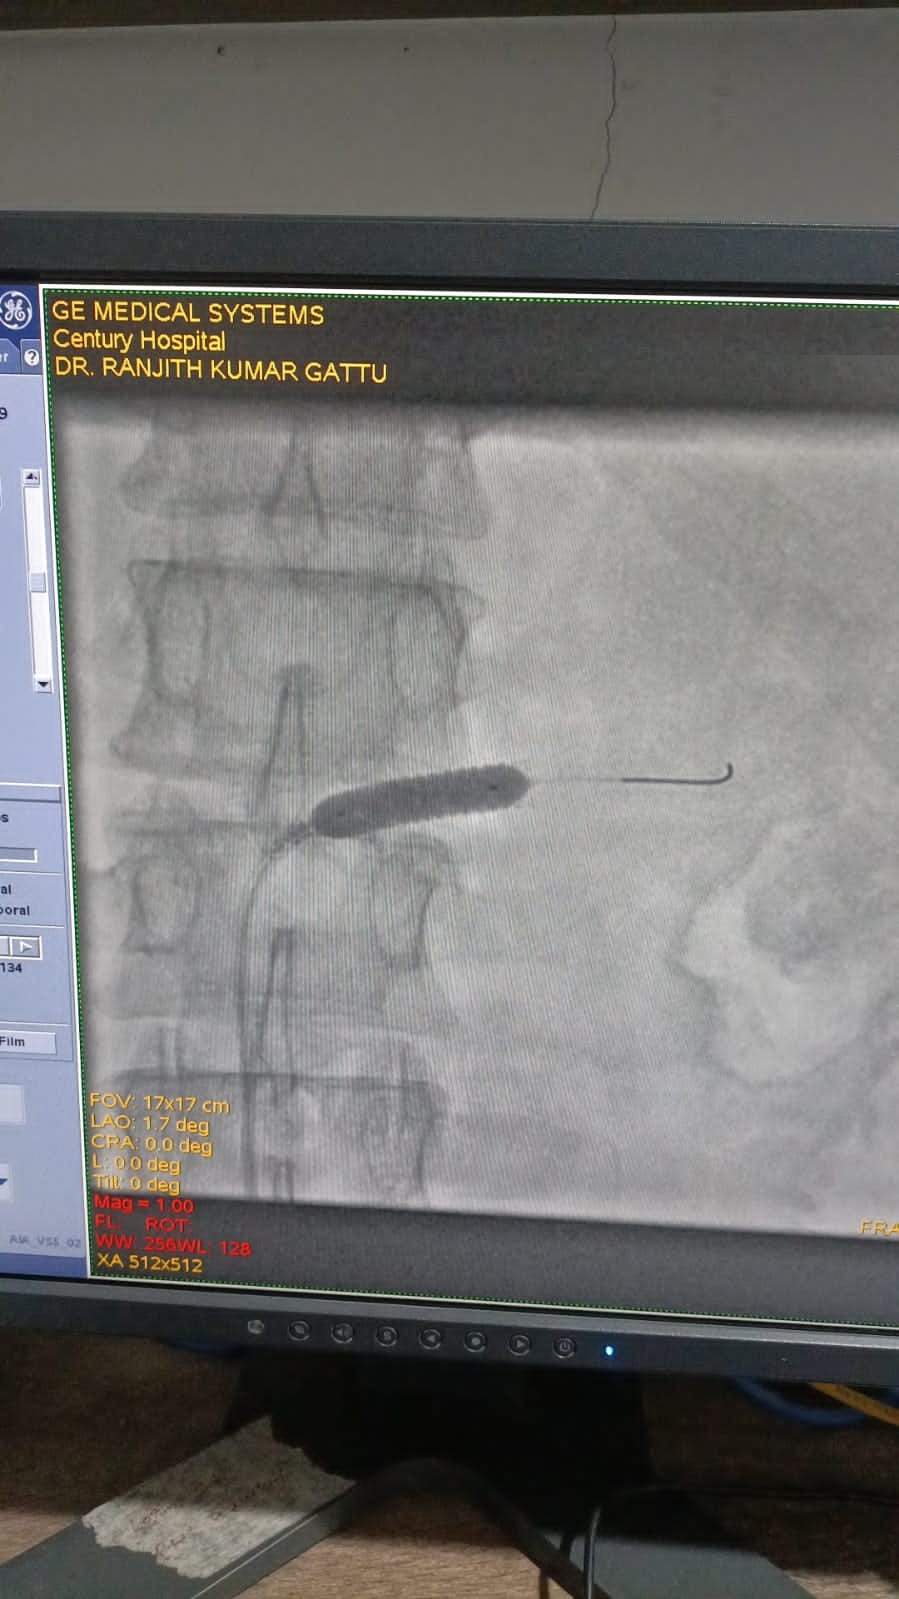

Left Coronary Diseased Artery

Right Coronary Diseased Artery